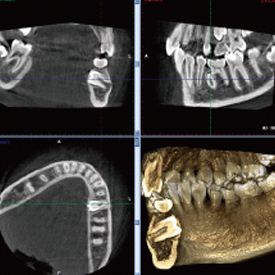

精度が高い診査・診断&安心・安全な治療歯科用CT- Computer Tomograghy -

CTとはComputer Tomograghyの略で、日本語ではコンピューター断層撮影と訳されます。

これは、X線とコンピューターによって、歯や骨の位置や形態などを3D画像で立体的に撮影するための医療機器です。

血管や神経の位置を立体的に把握し、骨量、骨密度を正確に確認できるため、インプラント治療の際にはCTによる診査・診断が必須となっています。

また、CTは、インプラント治療だけでなく、全ての歯科治療の精度向上に役立ちます。

歯槽骨の状態や根管の形態等をより正確に把握することができるため、埋伏歯抜歯、矯正治療、根管治療、歯周病治療など、さまざまな治療において、より正確な診査・診断、治療の高度化が期待できます。

多くの歯科医院では、CTを撮影するために外部のスキャニングセンターへ撮影に出向く必要がありますが、当クリニックでは院内にCTを設置しているため、レントゲンと同じように院内で撮影し、即座に診ることができます。